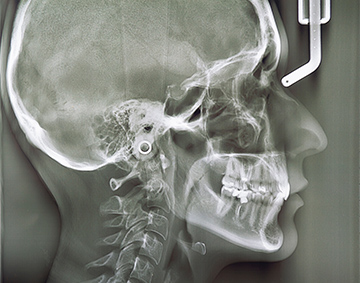

小児矯正は「いつ始めるか」が非常に重要です。当院では、まずフェイススキャンでお顔の情報を詳細に取得し、お子さんの成長の段階を正確に診断いたします。

データに基づき、お子さんに合わせた適切な治療をご提案し、「成長期」という大切な時期を逃さず、お子さんが本来持つ健やかでバランスの取れた顔立ちへと導きます。

01

各種先端設備を用いた精密検査

矯正治療において患者さんに合った治療計画の作成は重要であり、そのためには精度の高い検査が欠かせません。神戸の【のぶ歯科・歯ならび歯科】では歯科用CT検査やセファロ分析、フェイススキャン、気道検査などさまざまな評価を実施します。その結果から、お子さんの将来のことも考えて適切とされる治療内容をご提案いたします。